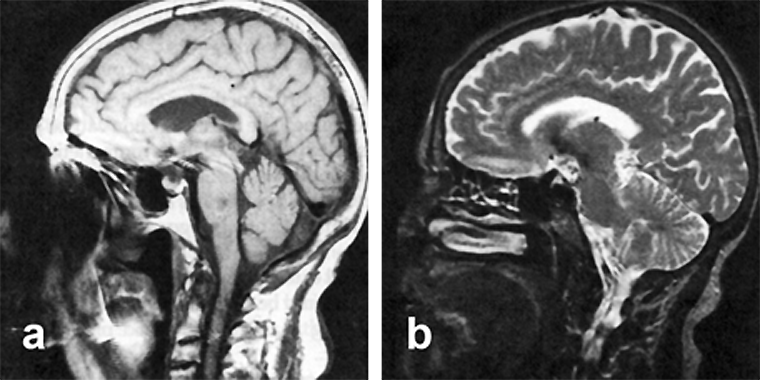

Figura 17-02:

Sagittal midline images through a head. (a) Intermediately weighted image, and (b) T2-weighted ima­ge. On the left ima­ge, a low signal in­ten­si­ty area is seen in the pons, suggesting a le­sion. This lesion is not visible on the T2-weighted ima­ge. It is caused by image distortion created by fer­ro­mag­ne­tic im­plants.